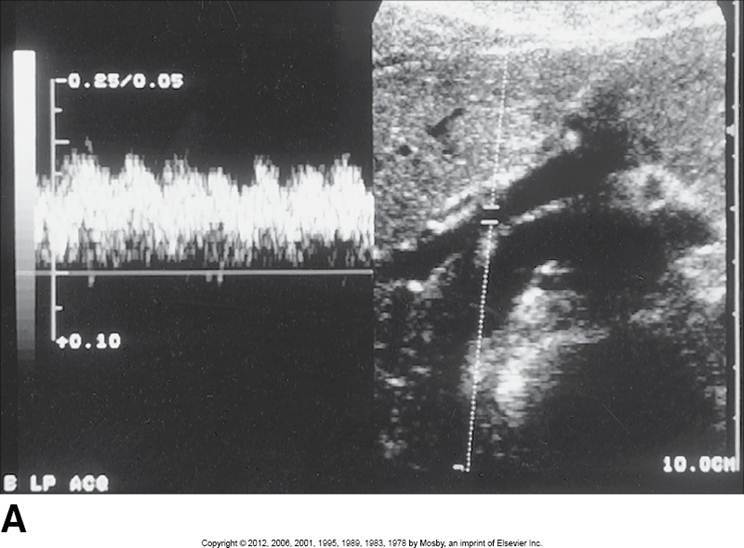

Proximal aorta

High systolic peak

Low diastolic comp.

Clean window